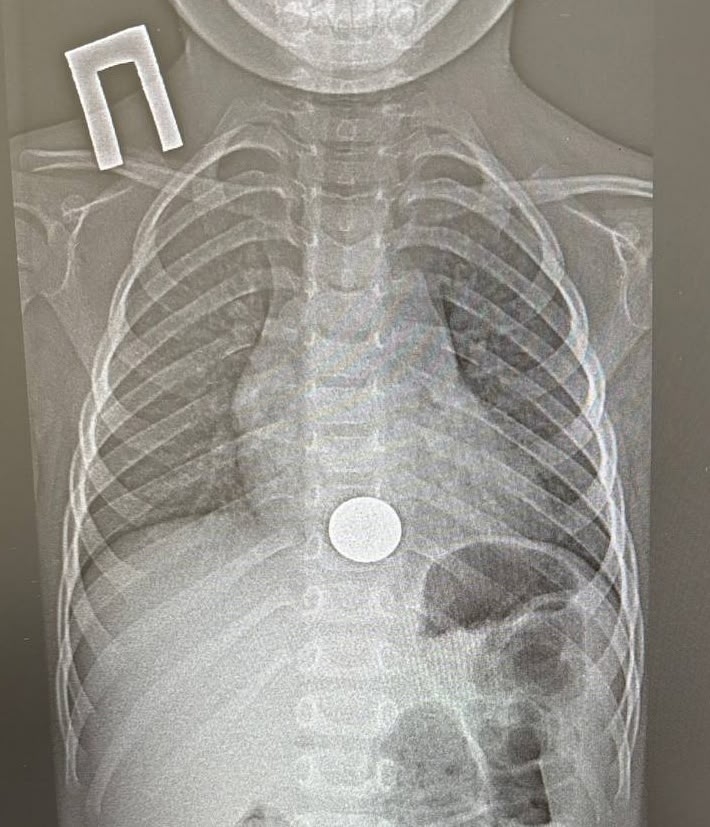

Татарстанские врачи спасли ребенка, который проглотил монету

Операция длилась всего минуту.

В Нижнекамскую детскую районную больницу срочно доставили трёхлетнего малыша, который случайно проглотил монету. Хирург-эндоскопист Игорь Шогоров провёл малотравматичную операцию и извлёк инородное тело из пищевода. Это заняло всего минуту. Уже на следующий день ребёнка выписали домой в удовлетворительном состоянии, сообщили в Минздраве Татарстана.

Медики советуют родителям тщательнее следить за детьми. Мелкие предметы, например, монеты, батарейки, магниты, стоит держать в труднодоступном месте.